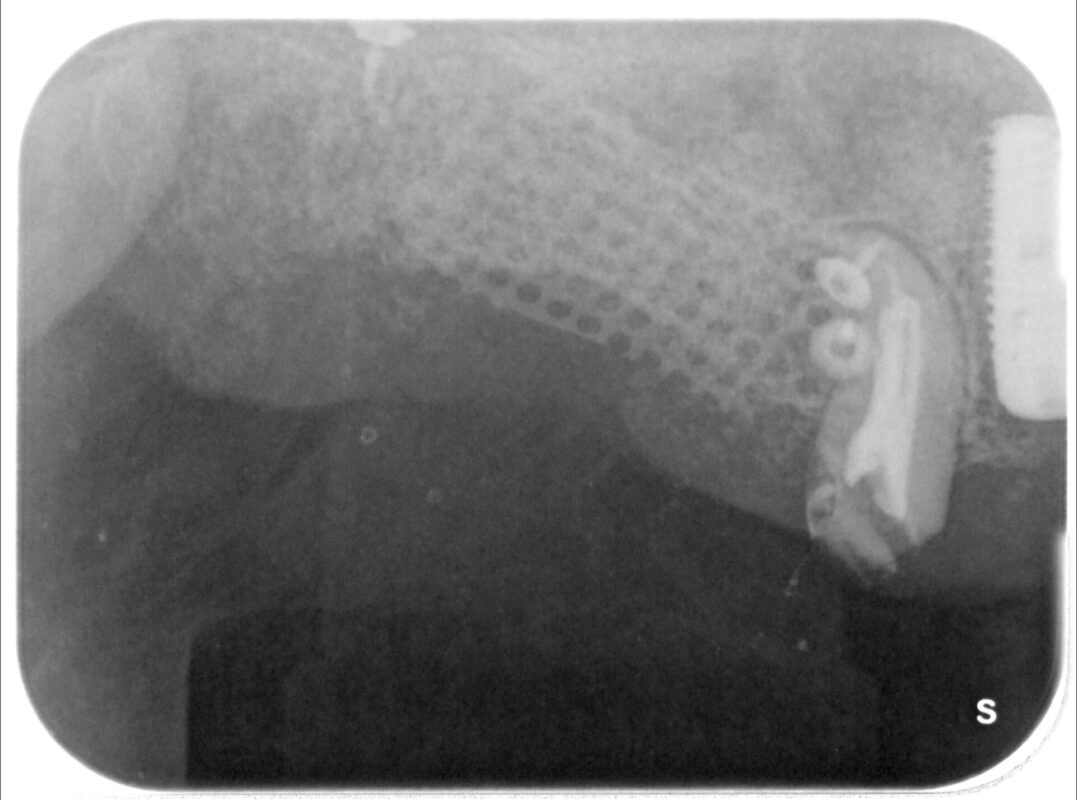

チタンメッシュによる防波堤のようなものを作製し、その中に人工骨=バイオスを入れて幅の増大とあ

る程度の高さを確保しました。

複雑なので詳細は省きますが、ソーセージテクニックの変法の私のオリジナル方法。

チタンメッシュによる骨造成時